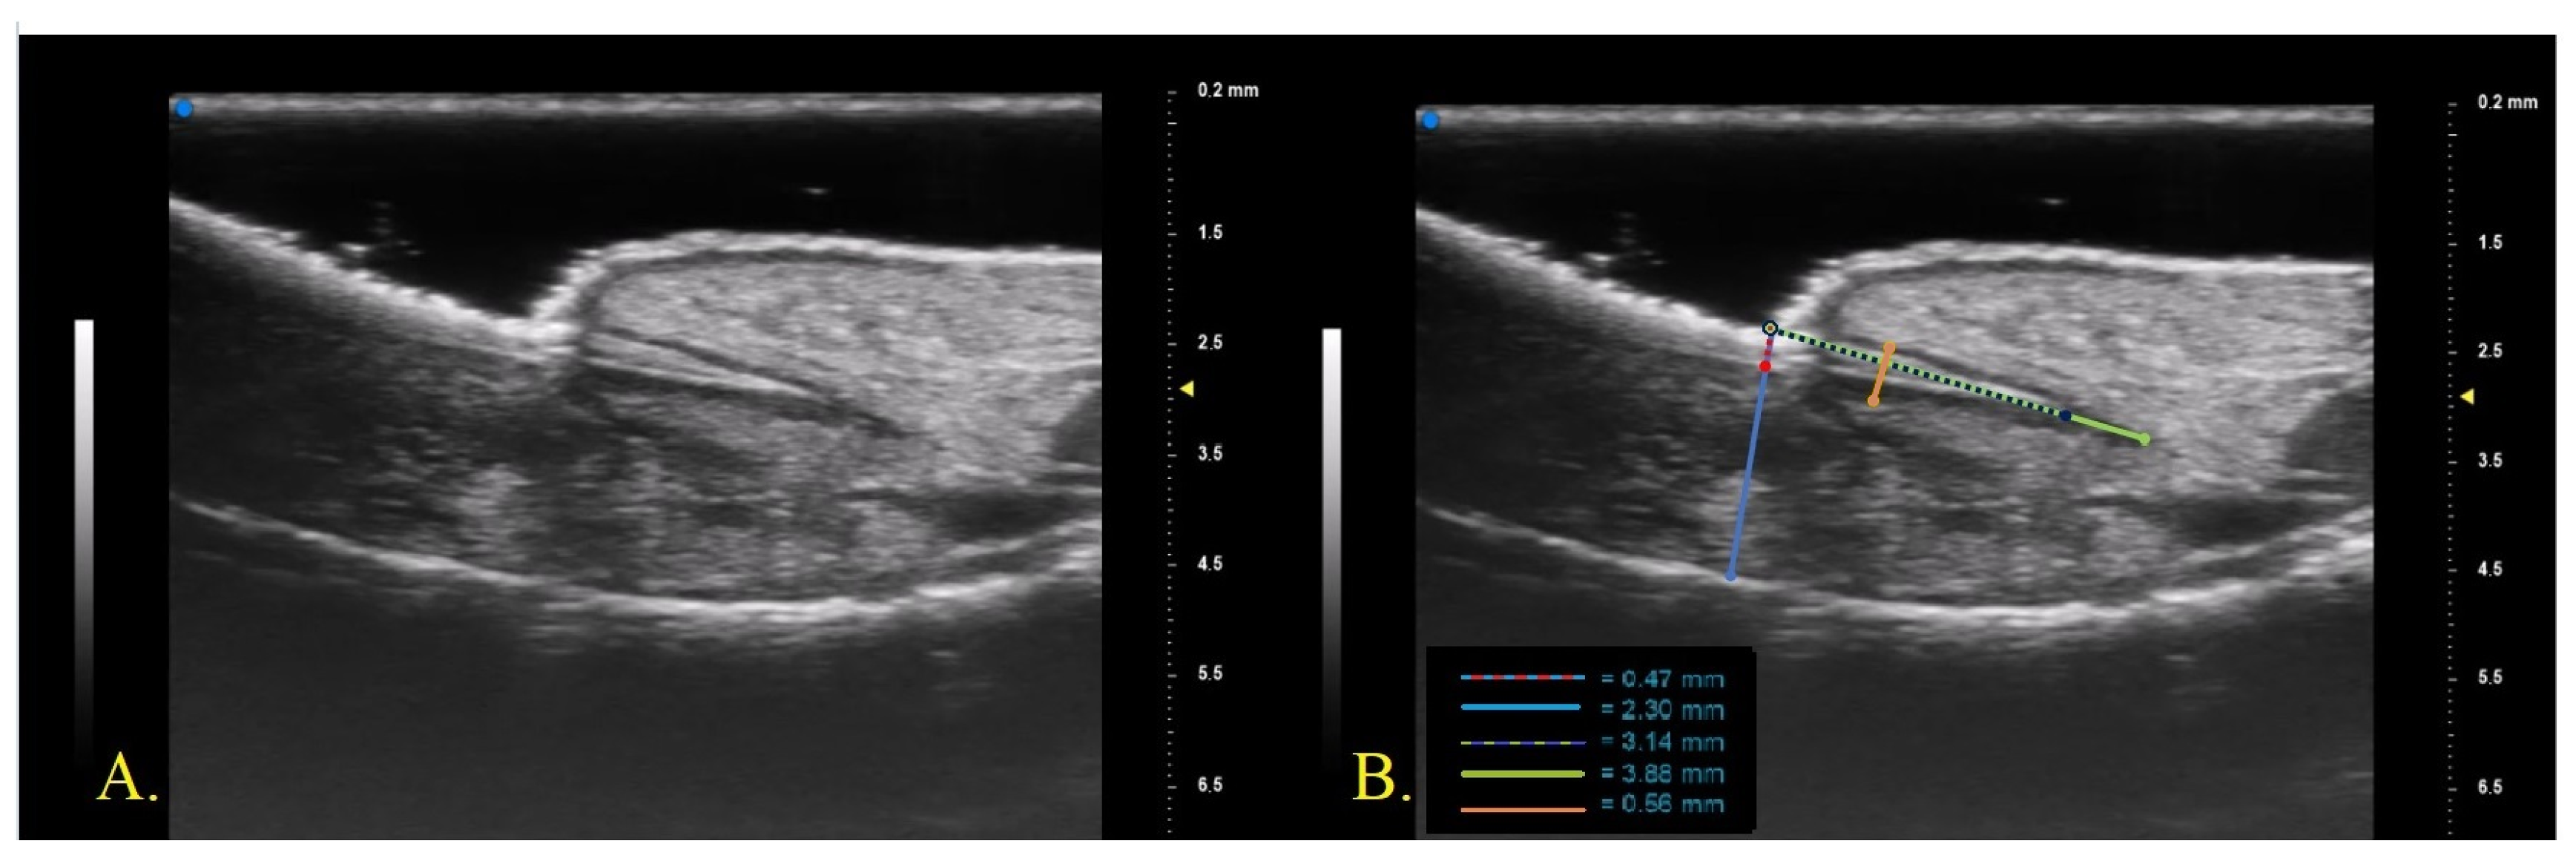

2. Materials and Method

We conducted a prospective single-center study enrolling 10 patients with psoriasis and psoriatic onychopathy, in the absence of psoriatic arthritis, who started therapy with monoclonal antibodies (mAb) directed against TNF-alpha, (IL)-17 and IL-23. The patients were naive to previous conventional and biologic systemic therapies and were evaluated at baseline and after 1 month and after 3 months from the beginning of biologic therapy. At each visit, the clinical investigation was performed by a dermatologist expert in psoriasis who collected a photographic record of the patient and assessed clinical disease parameters such as the psoriasis area severity index (PASI), NAPSI, modified (m)-NAPSI calculated on the nail with major clinical alterations and dermatology life quality index (DLQI) [21,22,23]. For the US examination of the nail apparatus, a UHFUS with a 70 MHz probe was used (Vevo MD®® FUJIFILM VisualSonics, Toronto, ON, Canada). UHFUS investigation was performed by a dermatologist expert in UHFUS blinded from the clinical diagnosis. The fingernail examination was performed in a seated position with hands placed on a table. The proper distance of the probe from the skin, to permit imaging of superficial structures, was maintained with an appropriate amount of gel [23]. The fingernail apparatus was assessed in B-MODE with a longitudinal section on the middle point of the lamina. For each patient, the first (I) and second fingers (II) of the right hand and the nail with the worst clinical aspect (W) were examined. The following parameters were measured three times by the same operator who performed the UHFUS examination and the average value of the three measurements was recorded (Figure 1)

• Nail plate thickness: measured as the maximum distance between the dorsal and ventral hyperechoic plates of the nail (measure A).

• Nail bed thickness: measured as the maximum distance between the ventral plate of the nail and the edge of the phalangeal bone (measure B).

• Nail plate insertion: the non-visible part of the nail plate measured from its proximal point to its distal point (measure C).

• Nail matrix length: measured from the insertion of the nail plate to the proximal point of the matrix (measure D).

• Nail matrix thickness: measured at the point of maximum matrix thickness (measure E).

Figure 1. (A). UHFUS nail morphology; (B). UHFUS structural features measured: nail plate thickness, red-blue dotted line (measure A); nail bed thickness, blue line (measure B); nail plate insertion, purple-green dotted line (measure C); nail matrix length, green line (measure D); nail matrix thickness, orange line (measure E).